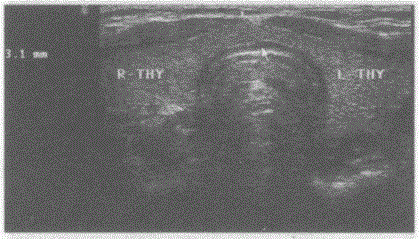

请回答箭头所指部位的解剖名称:A.甲状腺峡部B.甲状腺左叶C.甲状腺右叶D.气管

问题 请回答箭头所指部位的解剖名称:

选项 A.甲状腺峡部 B.甲状腺左叶 C.甲状腺右叶 D.气管

答案 A